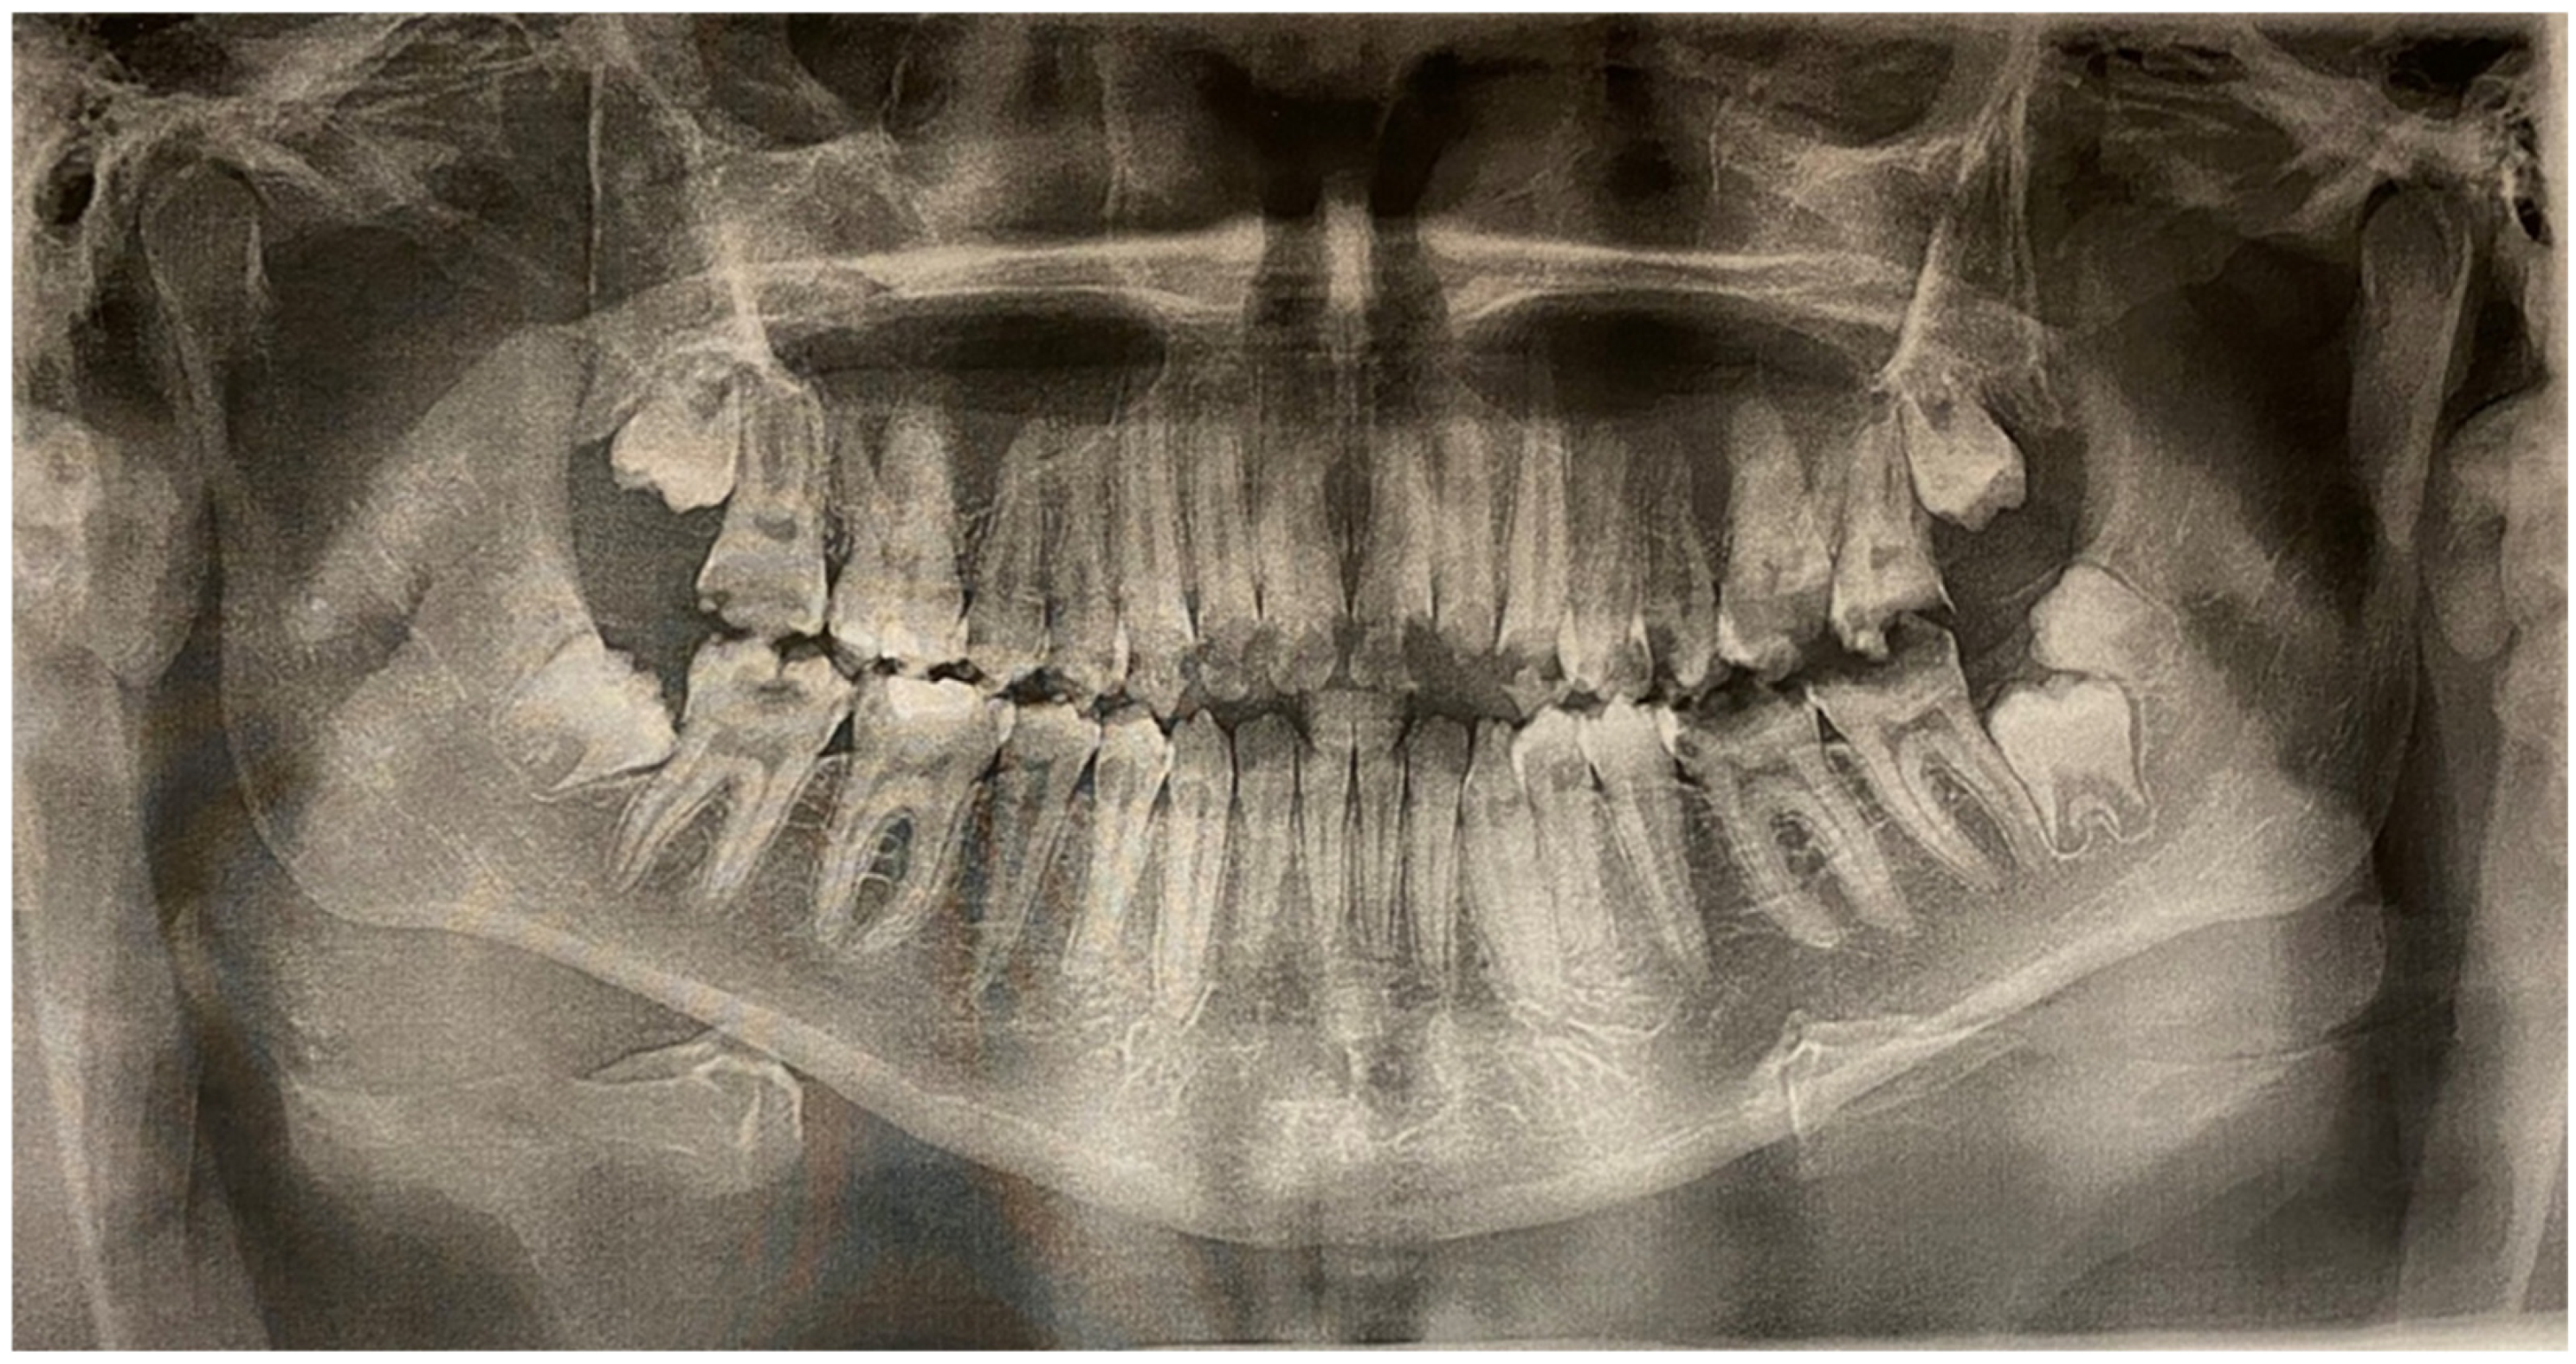

2. Case Report